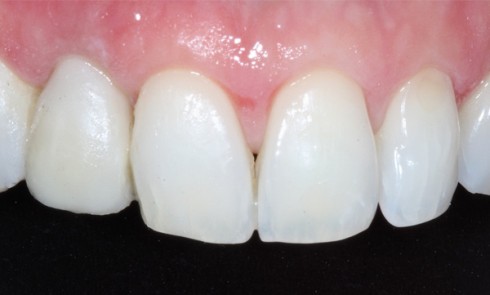

Article réservé à nos abonnés Techniques de transfert du profil d’émergence lors de la confection de la prothèse d’usage

Le profil d’émergence de la couronne est : – créé au laboratoire ou au cabinet lors de la confection de la...